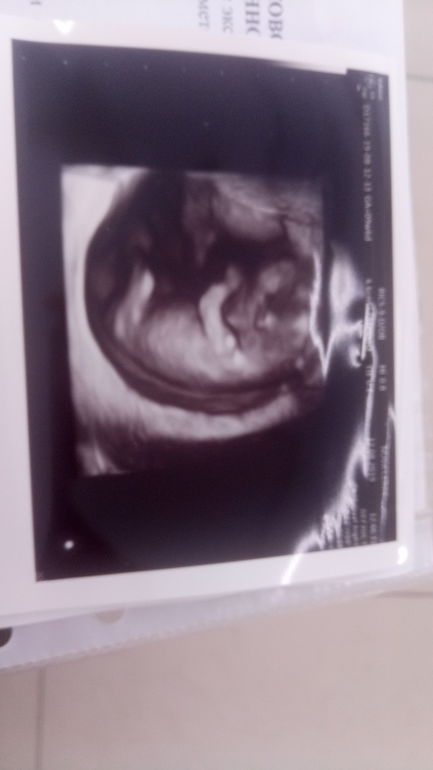

Узи 9 недель 6 дней) позавчера

Какая красивая фоточка)) у меня сегодня 9.6..буду представлять что мой такой же карапуз)) Все-таки экспертное - есть экспертное узи...👍

Экспертное узи в новаклиник

Это я Вас, наверное, вчера напугала своей историей... :( Извините, не хотела! Но я сама до сих пор прийти в себя не могу. А скажите, пожалуйста, что это у вас за УЗИ такое?!? Я видела УЗИ 3D, но они другого цвета, и к тому же, я думала, что их делают только на позднем сроке. А ребёночек у Вас замечательный!

Спасибо большое! Это экспертное узи в новаклиник. Я рада, что у Вас всё обошлось!!!!